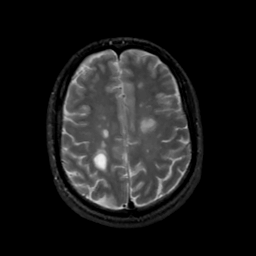

MR Study #10, April 28, 1991 -- Slice #36